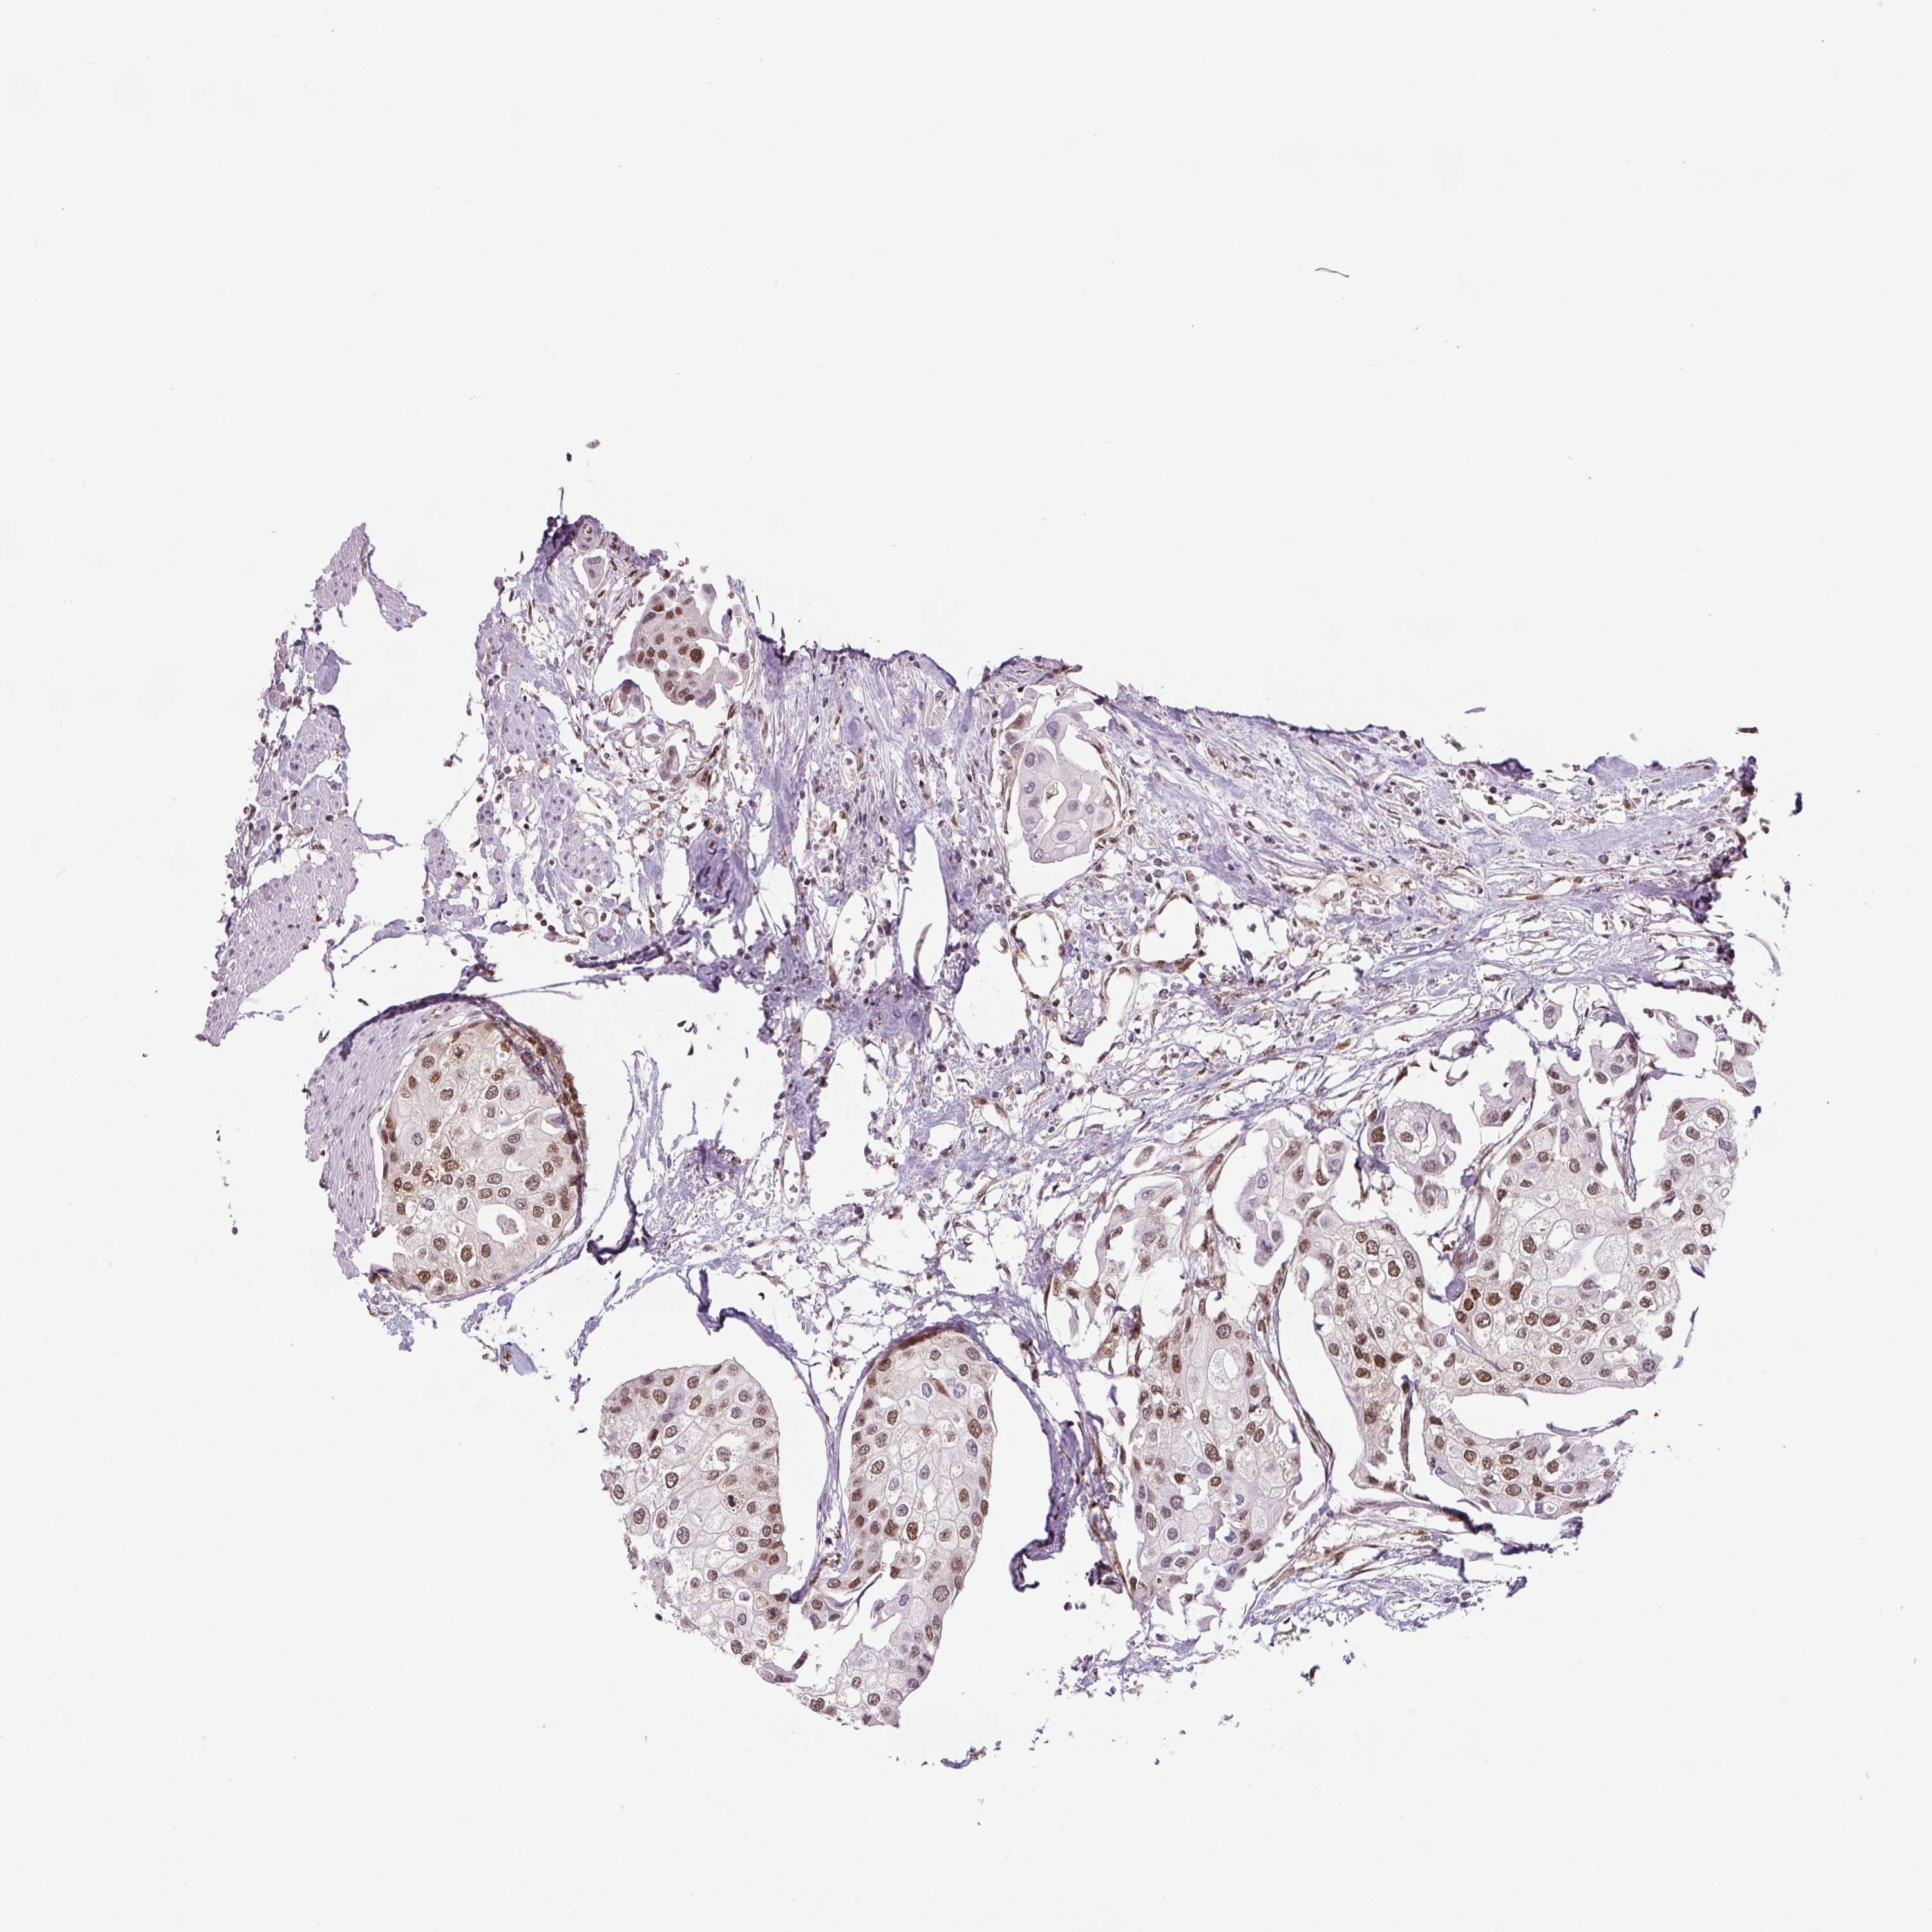

UROTHELIAL CANCER - Protein expressioni

A mouse-over function shows sample information and annotation data. Click on an image to view it in a full screen mode. Samples can be filtered based on level of antibody staining by selecting one or several of the following categories: high, medium, low and not detected. The assay and annotation is described here.

Note that samples used for immunohistochemistry by the Human Protein Atlas do not correspond to samples in the TCGA dataset.

Antibody stainingi

Antibody staining in the annotated cell types in the current human tissue is reported as not detected, low, medium, or high, based on conventional immunohistochemistry profiling in selected tissues. This score is based on the combination of the staining intensity and fraction of stained cells.

Each image is clickable and will lead to virtual microscopy that enables deeper exploration of all samples and also displays staining intensity scores, fraction scores and subcellular localization as well as patient and tissue information for each sample.

Antibody HPA008784

Antibody CAB033036

Antibody CAB058691

Staining

High

Medium

Low

Not detected

Intensity

Strong

Moderate

Weak

Negative

Quantity

>75%

75%-25%

<25%

None

Location

Nuclear

Cytoplasmic/membranous

Cytoplasmic/membranous,nuclear

Urothelial carcinoma, Low grade

Urothelial carcinoma, High grade

Urothelial carcinoma, NOS